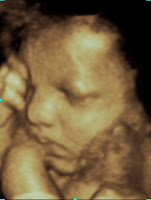

An Indepth View From Within A Little Insight 3d 4d Ultrasound